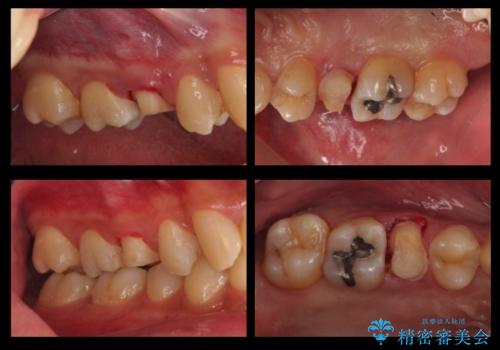

- 放置した虫歯の治療で来院。

歯茎の中まで虫歯になっており、そのまま完璧に治療をすることは不可能でした。

開始前

治療途中